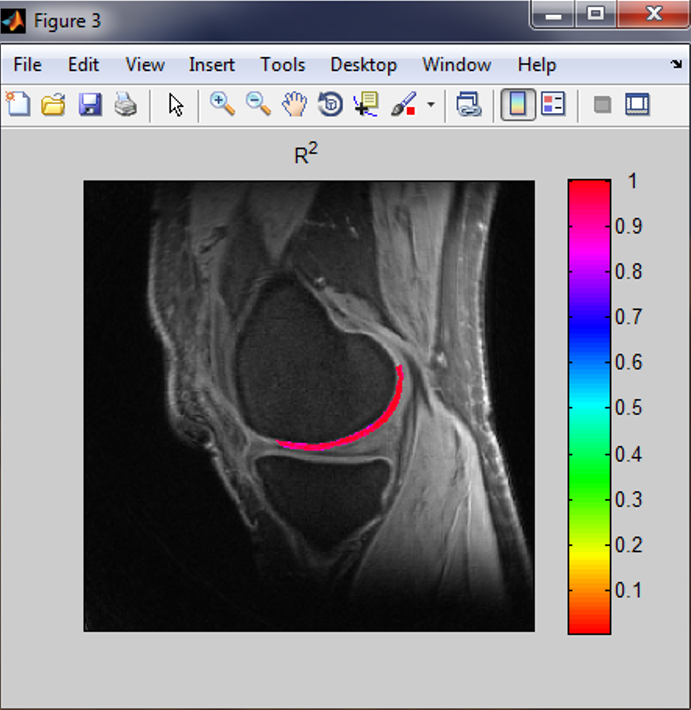

pM1 is a MATLAB-based standalone deployment which can run in a personal computer without MATLAB installed in it. pM1 is used to perform T2/T2*/T1rho mapping on MRI images in DICOM format. pM1 performs curve fitting to a model of one-term exponential decay, s(t) = A*exp(-t/T2) + n(t), on a pixel-by-pixel basis in a region of interest (ROI). It produces three maps: T2 (T2* or T1rho) map, intensity A map, and R-square (R2) map. pM1 also calculates the mean and standard deviation (SD) of T2 (T2* or T1rho) in a user-defined ROI. This software package includes a user manual which details how to install and run pM1 on your computer. pM1 has no function for motion correction.

Figure 1. pM1 software and its output maps. (a) pM1 panel, (b) T2* map, (c) A map, and (d) R2 map.